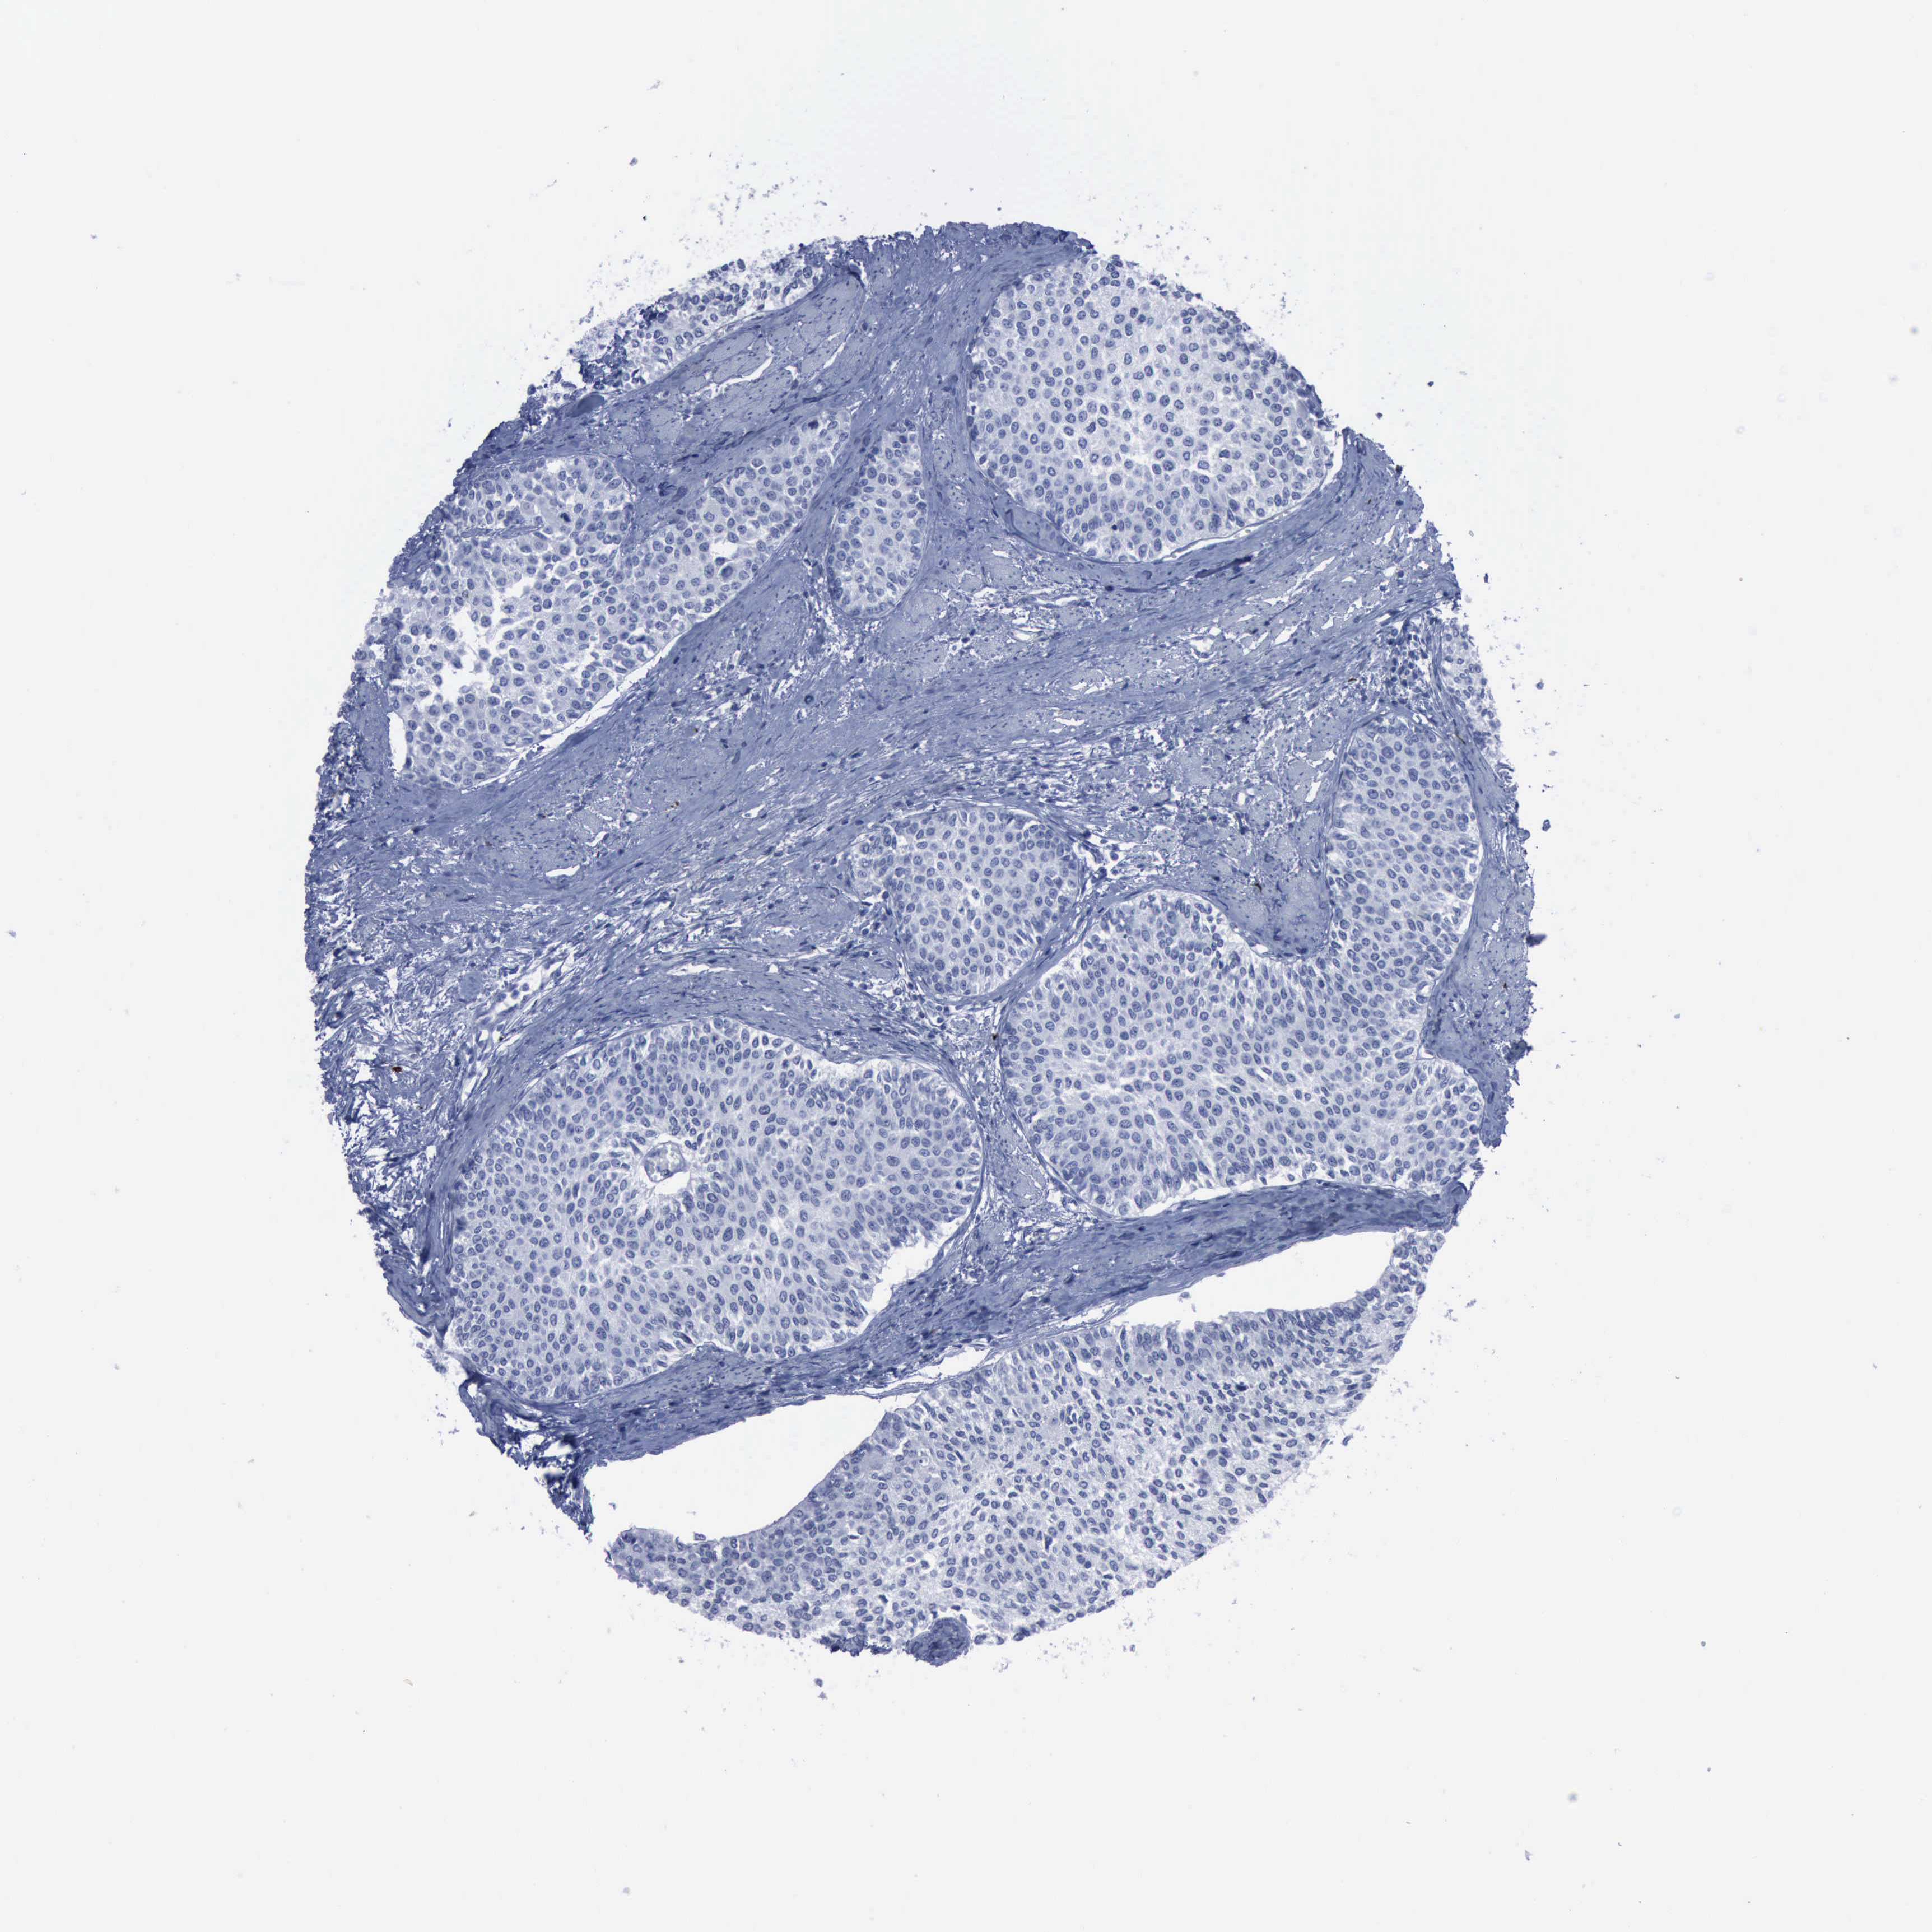

UROTHELIAL CANCER - Protein expressioni

A mouse-over function shows sample information and annotation data. Click on an image to view it in a full screen mode. Samples can be filtered based on level of antibody staining by selecting one or several of the following categories: high, medium, low and not detected. The assay and annotation is described here.

Antibody stainingi

Antibody staining in the annotated cell types in the current human tissue is reported as not detected, low, medium, or high, based on conventional immunohistochemistry profiling in selected tissues. This score is based on the combination of the staining intensity and fraction of stained cells.

Each image is clickable and will lead to virtual microscopy that enables deeper exploration of all samples and also displays staining intensity scores, fraction scores and subcellular localization as well as patient and tissue information for each sample.

Antibody HPA004765

Urothelial carcinoma, High grade

Urothelial carcinoma, Low grade